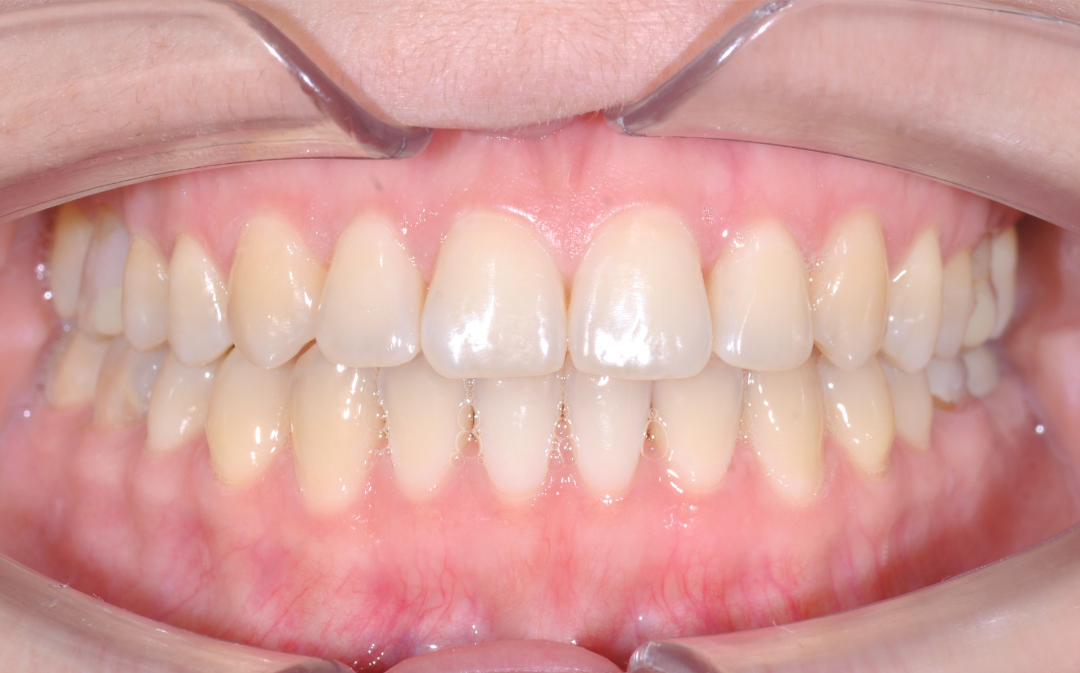

Результаты комплексного лечения

Комплексный подход команды «Архитектор Улыбок» дал закономерный результат, который был спрогнозирован еще

до старта лечения.

Здоровая улыбка

Ушел дискомфорт в суставе, исчезли боли в процессе жевания. Нижняя челюсть заняла стабильное, физиологичное положение.

Восстановилась функция

Качество жевания кардинально повысилось, процесс приема пищи снова стал комфортным.

Эстетика

Исправлен прямой прикус, восстановлена форма резцов, а улыбка стала не только красивой, но и здоровой с точки зрения биомеханики.